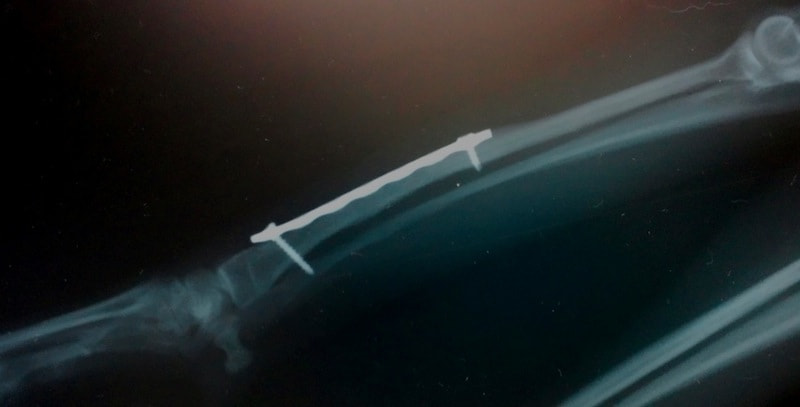

他院にて左大腿骨遠位の成長板骨折(salter-harrisⅠ型)が認められており、治療相談を目的として来院。当院にて、キルシュナーワイヤーを用いたピンニングにより骨折部位の整復を行いました。術後の経過は良好で、現在も経過観察中です。

術後レントゲン

Arthrex社のターゲティングデバイスを用いてピンニングの位置を調整することで、確実な固定を行っています。当院ではこの手術器具以外にも、人の手術にも使用される様々な器具を導入し、手術精度を高め、また医療メーカーと新しい器具の開発、試作にも取り組んでおります。